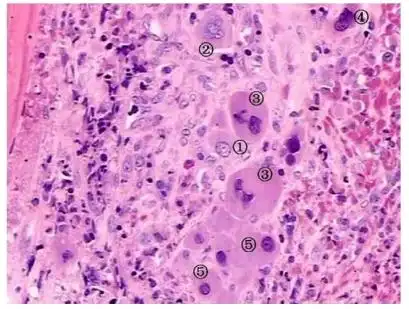

图13 骨切片示成骨细胞(蓝)和骨陷窝(绿)

成骨细胞又称为骨母细胞,是形成骨组织的细胞,能合成和分泌骨基质,并

骨组织的细胞有四种(图5-7): (图5-7 骨组织的细胞示意图) (1)骨 祖

【求助】求助骨组织切片he染色后能区分开破骨细胞和成骨细胞吗?